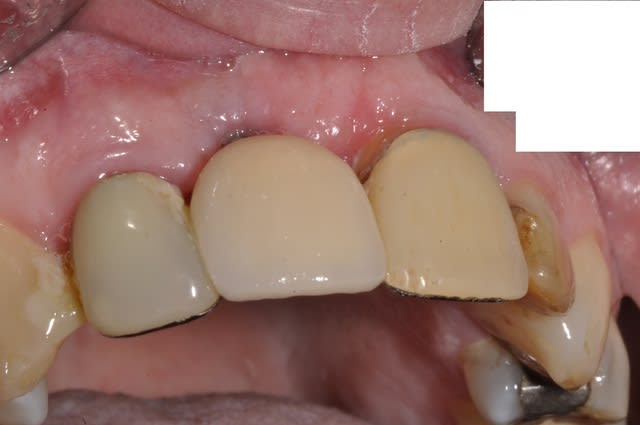

comme promis Céramic

Controle et pose 15 jours apres du fx moignon vendredi dernier entre les deux L'APN en panne

provisoire avec diastème en bouche, suis pas certain que cela va lui plaire

Moi c'est le collet qui ne me plait pas,donc une provisoire çà m'arrange

les 12 et 21 sont toujours d'avant 1992!

CCM posée il y a un mois

plus de diasteme, c'était bien la peine, l'hygiene toujours au top et la gencive a adoré l'aller retour

par contre l'implant lui RENDRA SERVICE

Céramik comme promis Ma réponse en image 2ans après

3 Rx le jour de la POSE de la dent

4 La dent le jour de la pose

6 Rx aujourd'hui

7 La dent 2ans après